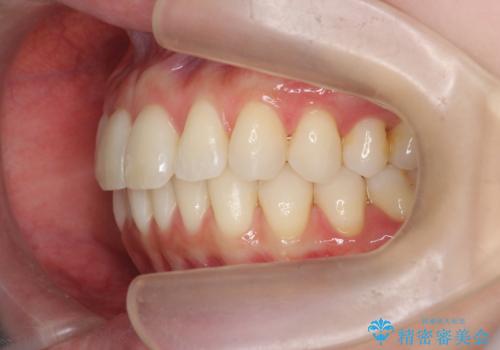

昔ワイヤー矯正をして後戻りした 軽度のがたつき モニター矯正

- 矯正治療後の後戻りを主訴に来院。

特に下の前歯のがたつきを気にされていました。

マウスピース矯正で再矯正を行いました。

再度の後戻りを防ぐため、下顎前歯の裏にはワイヤーを貼る保定を行っています。